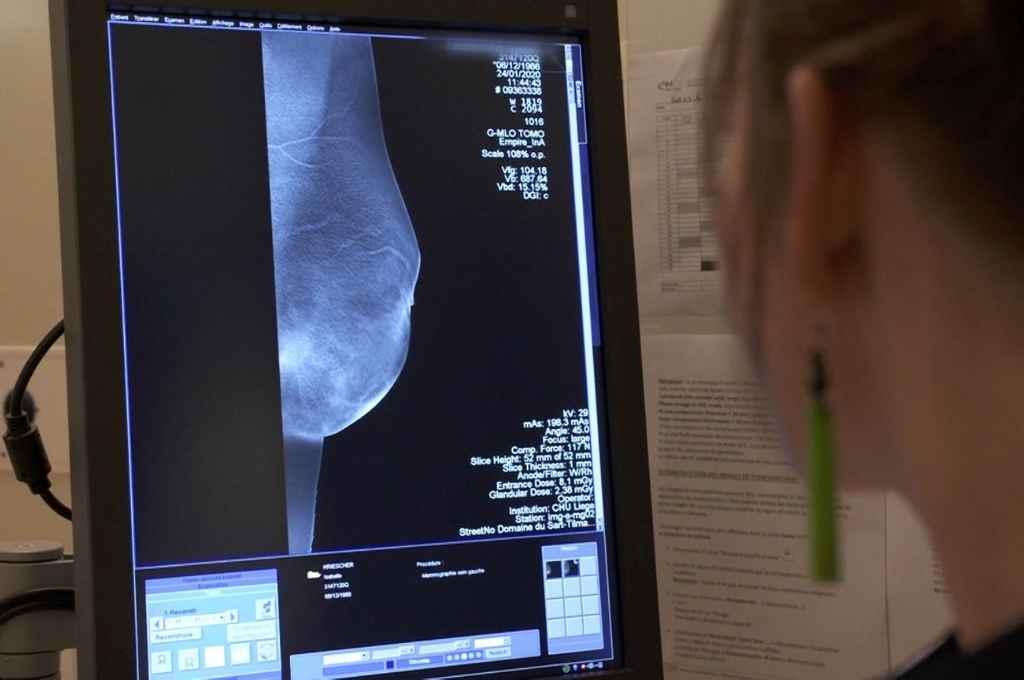

Cáncer de mama. "Es el tumor maligno más frecuente. Afecta fundamentalmente a mujeres mayores de 50 años aunque existen casos de diagnóstico en menores de dicha edad. La mamografía es el estudio por excelencia que permite detectar el cáncer de mama en estadios tempranos y curar a más del 90% de las mujeres que se diagnostican". El porcentaje de curación de estos tumores disminuye drásticamente cuando no se cuenta con diagnóstico temprano y no se establece un tratamiento específico.

De acuerdo a los datos de la Agencia, "el impacto de la pandemia en esta enfermedad fue muy profundo: con 70% promedio de reducción de los estudios, se contabilizaron solo en 3 meses 7 mil mamografías menos que en el 2019, lo cual hace estimar que en el 2020 se realizaron por lo menos 30 mil estudios mamográficos menos que en el año anterior a la pandemia.

En la ciudad de Santa Fe se encuentra la Unidad Funcional de Mama (UFM), unidad interdisciplinaria que nuclea la lectura y procesos de diagnóstico de todas las mujeres con cáncer de mama de la salud pública de la provincia en la región centro y norte. "Hemos detectado, según la experiencia de esta unidad, que un estudio es positivo cada 182 que se realizan. Por lo tanto, la severa reducción en el número de estudios mamográficos realizados en 2020 podría traer un impacto negativo en las tasas de mortalidad por esta enfermedad en un futuro".

Por ello la agencia de control del cáncer habilitó un número de whatsapp de la Unidad Funcional de Mama, para solicitar turnos de forma sencilla para aquellas mujeres que se encuentran en la edad objetivo para realizar estudios de screening, mujeres entre 50 y 75 años que no se hayan realizado su mamografía o que la última fue hace más de un año.

También se realizan actividades de difusión en redes sociales y centros de atención primaria de toda la provincia fomentando la realización del estudio y el autoexamen mamario así como la consulta urgente si se detecta algún nódulo o tumor en la mama.